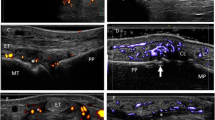

The device used was a color power Doppler (PD) US (Philips IU22). Depending on the depth of joint, the probe frequency was set at 3–9 or 5–12 MHz, and the musculoskeletal condition was chosen. The sonographer examined all target joints, tendons, bursae, and nails in grayscale mode and detected the blood flow signals in PD mode. The grayscale pattern showed structural changes and the gain was set at maximum sensitivity without noise signals. The PD pattern showed the activity level of inflammation and its gain was set at maximum sensitivity without Doppler artifact and color overflow.

For joints, joint effusion, synovial thickening, PD signals, osteophytes, and bone erosions were evaluated. Similarly, for tendons, enthesitis (entheses thickening, hypoechogenicity, PD signals, osteophytes, calcifications, and bone erosions), tendon sheath synovial thickening, and tendon sheath effusion were evaluated. With respect to bursae, the sonographer evaluated bursa synovial thickening and bursa effusion. Regrading nail dystrophy, the sonographer mainly observed whether there was thickening of the nail plate structure, surface unevenness, and disappearance of the deep nail plate and whether the echogenicity and blood flow signal of nail bed and nail matrix were altered.

Among these variables, joint effusion, joint synovial thickening, and joint PD signals were semiquantitatively assessed. The joint effusion and joint synovial thickening were scored as follows [19]: grade 0 (no anechoic, hypoechoic, or hyperechoic structure was visible, which means no effusion/synovial thickening), grade 1 (joint effusion/synovial thickening did not exceed the peripheral trigonum of the bones adjacent to the scanned joint), grade 2 (joint effusion/synovial thickening extended beyond the articular cavity but did not reach the backbone), grade 3 (joint effusion/synovial thickening extended beyond the articular cavity and reached the backbone). The grade of unilateral multi-joints (such as MCP, MTP, and IP) were recorded with the highest score. Finally, for joints with synovial thickening, the joint PD signals were scored following the following criteria [20]: grade 0 (no intra-articular blood flow signals), grade 1 (no more than three blood flow signals), grade 2 (a small amount of blood flow signals, the area was less than 50% of the synovial area), grade 3 (continuous blood flow signals, the area exceeded 50% of the synovial area). Likewise, the grades of unilateral multi-joints (such as MCP, MTP, and IP) were recorded with the highest score.

The top ten most common affected anatomical sites of PsA are quadriceps tendon, MTP, Achilles tendon, proximal interphalangeal joint (PIP), knee, MCP, ankle, wrist, distal interphalangeal joint (DIP), and shoulder with the prevalence of 55.17%, 54.02%, 50.57%, 47.89%, 46.74%, 39.85%, 32.57%, 27.20%, 24.14%, and 20.69%, respectively (Fig. 1).

Moreover, in this study, we also concluded that the most common affected anatomical sites of patients with PsA were quadriceps tendon, MTP, Achilles tendon, PIP, and knee, which is similar to the findings of most previous studies [28, 29]. When conducting clinical and imaging examinations for patients with psoriasis, clinicians should pay more attention to these anatomical sites. Additionally, in patients with psoriasis without clinically confirmed arthritis, several subclinical ultrasound abnormalities including joint effusion, joint synovial thickening, joint PD signals, joint osteophytes, entheses hypoechogenicity, and tendon sheath effusion were detected, which is consistent with a number of previous studies showing that subclinical synovitis and enthesopathy exist in patients with psoriasis with no musculoskeletal symptoms and signs [21, 30,31,32,33]. In addition, in this study, we found no statistically significant difference between the PsA and non-PsA groups for nail dystrophy. In the past, several studies suggested that nail dystrophy was associated with a higher likelihood of PsA [34, 35]. However, Eder and his colleagues [36] found that only nail pitting was a strong predictor of PsA progression, while nail onycholysis was not associated with the development of PsA. This suggests that using only nail dystrophy to predict the development of PsA is inadequate, and further research in the future is needed to investigate which subtype of nail dystrophy could effectively predict the progression of PsA.